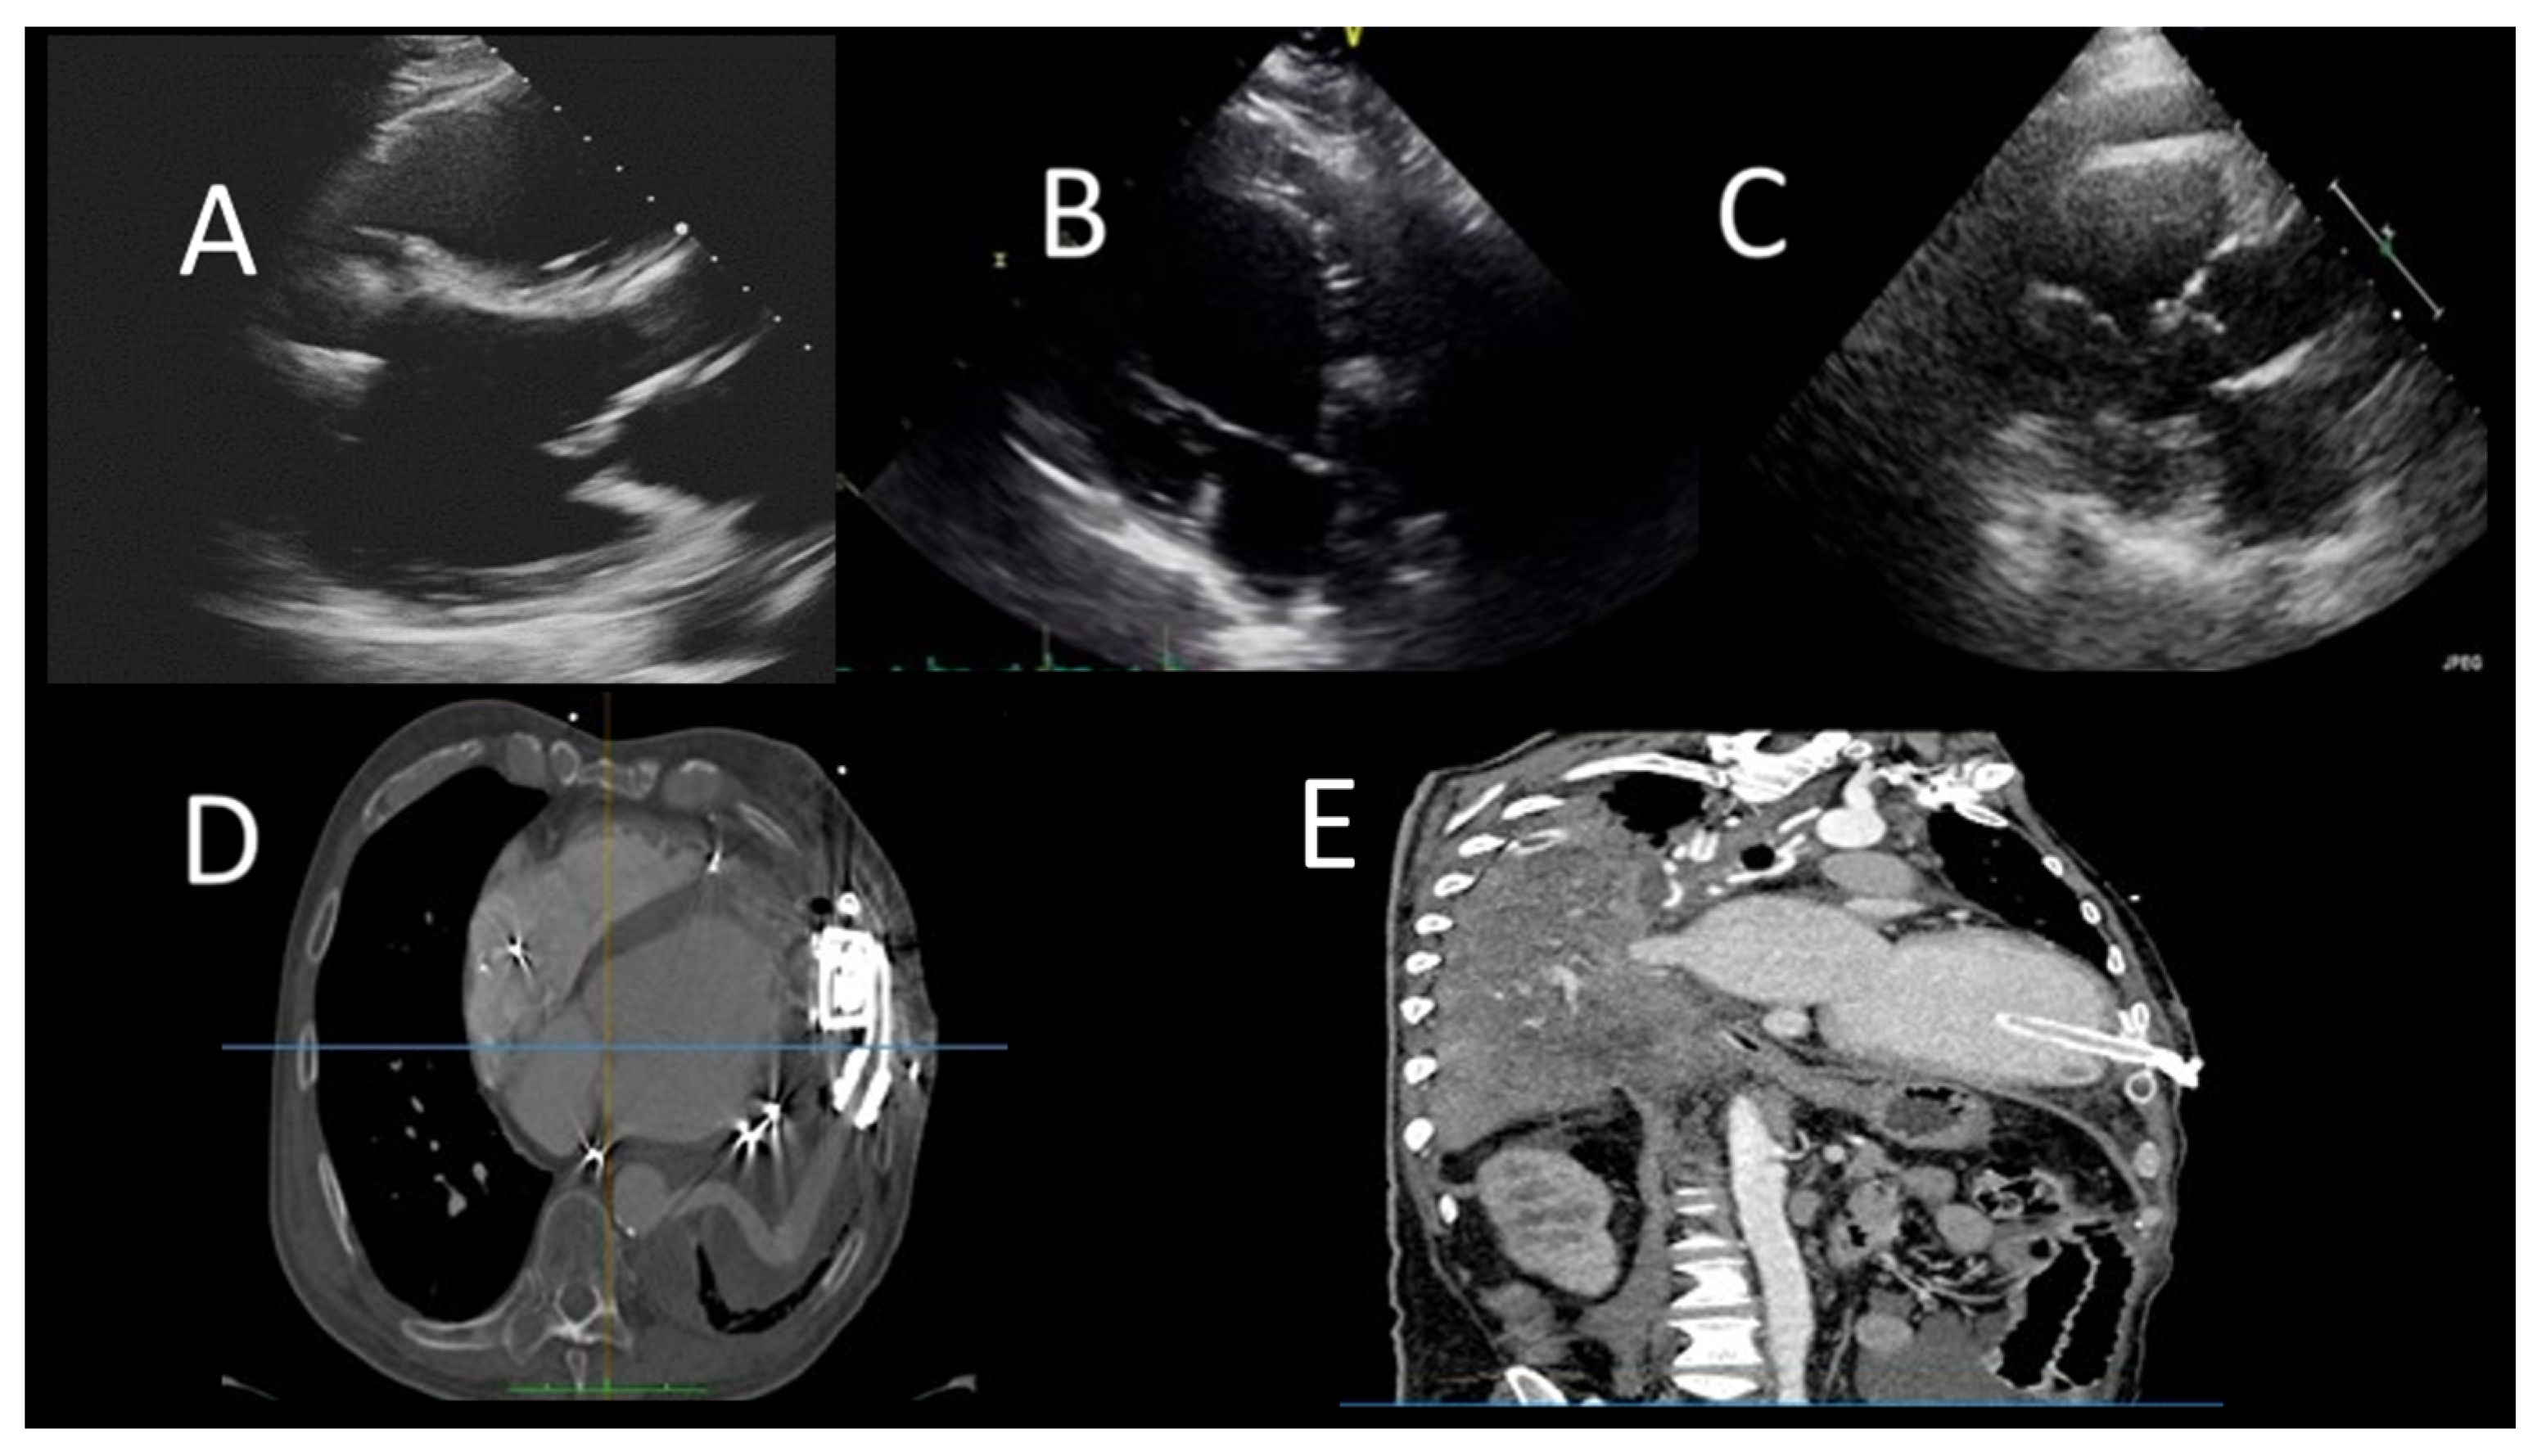

2.2.2. The Impella

2.2.3. The Veno-Arterial Extracorporeal Membrane Oxygenation

- Zein, R.; Patel, C.; Mercado-Alamo, A.; Schreiber, T.; Kaki, A. A Review of the Impella Devices. Interv. Cardiol. 2022, 17, e05. [Google Scholar] [CrossRef]

- Sef, D.; Kabir, T.; Lees, N.J.; Stock, U. Valvular complications following the Impella device implantation. J. Card. Surg. 2021, 36, 1062–1066. [Google Scholar] [CrossRef]

- Anand, S.; Barry, T.; Arsanjani, R.; LeMond, L. Echocardiography in Cardiac Assist Devices. Rev. Cardiovasc. Med. 2022, 23, 253. [Google Scholar] [CrossRef]

- Crowley, J.; Cronin, B.; Essandoh, M.; D’Alessandro, D.; Shelton, K.; Dalia, A.A. Transesophageal Echocardiography for Impella Placement and Management. J. Cardiothorac. Vasc. Anesthesia 2019, 33, 2663–2668. [Google Scholar] [CrossRef] [PubMed]

- Pieri, M.; Pappalardo, F. Bedside insertion of impella percutaneous ventricular assist device in patients with cardiogenic shock. Int. J. Cardiol. 2020, 316, 26–30. [Google Scholar] [CrossRef]

- Swedzky, F.; Barbagelata, A.; Perrone, S.; Kaplinsky, E.; Ducharme, A. Emerging concepts in heart failure management and treatment: Circulatory support with extracorporeal membrane oxygenation (ECMO). Drugs Context 2023, 12, 2022-7-7. [Google Scholar] [CrossRef] [PubMed]

- Hockstein, M.A.; Singam, N.S.; Papolos, A.I.; Kenigsberg, B.B. The Role of Echocardiography in Extracorporeal Membrane Oxygenation. Curr. Cardiol. Rep. 2023, 25, 9–16. [Google Scholar] [CrossRef]

- Platts, D.G.; Sedgwick, J.F.; Burstow, D.J.; Mullany, D.V.; Fraser, J.F. The Role of Echocardiography in the Management of Patients Supported by Extracorporeal Membrane Oxygenation. J. Am. Soc. Echocardiogr. 2012, 25, 131–141, Erratum in J. Am. Soc. Echocardiogr. 2012, 25, 427. [Google Scholar] [CrossRef]

- Kim, D.; Jang, W.J.; Park, T.K.; Cho, Y.H.; Choi, J.-O.; Jeon, E.-S.; Yang, J.H. Echocardiographic Predictors of Successful Extracorporeal Membrane Oxygenation Weaning After Refractory Cardiogenic Shock. J. Am. Soc. Echocardiogr. 2021, 34, 414–422.e4. [Google Scholar] [CrossRef]